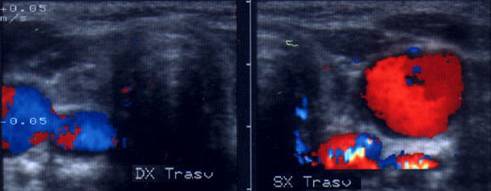

Voluminoasa tumefactie laterocervicala dreapta (16 cc ) si paratraheala stanga

(3 cc), pozitiva la citoaspiratie pentru recidiva de neoplazie papilara.

Aceeasi de

65 ani. Nu se evidentiaza vascularizatie intratumorale

Femeie de 29 ani. Linfonodul in regiunea

laterocervicala dreapta ( 7x12x23mm, 1 cc) in neoplazie papilara a tiroidei. Structura

parenchimatoasa, neomogenea, cu margini

nete, cu absenta hilului.Examen citologic: metastaza de neoplazie papilara.

Lob drept,

proiectie trasversala si longitudinala

Aceeasi pacienta. Nodul de consistenta dura in lobul

drept spre istm.

Ecografia: nodul cu margini indistinte care deformeaza marginea anterioara a glandei,

parenchimatoasa, neomogena, hipoecogena. Prezenta de linfonodi laterocervicali.

Ctoaspiratie: carcinom papilar.